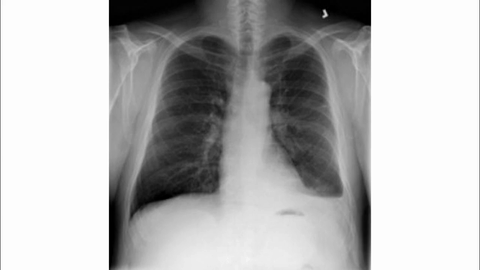

Reasoning Video Showcase

12Medical1.15 ± 1.171.56 ± 1.410.27 ± 0.390.30 ± 0.582.08 ± 1.561.81 ± 1.42